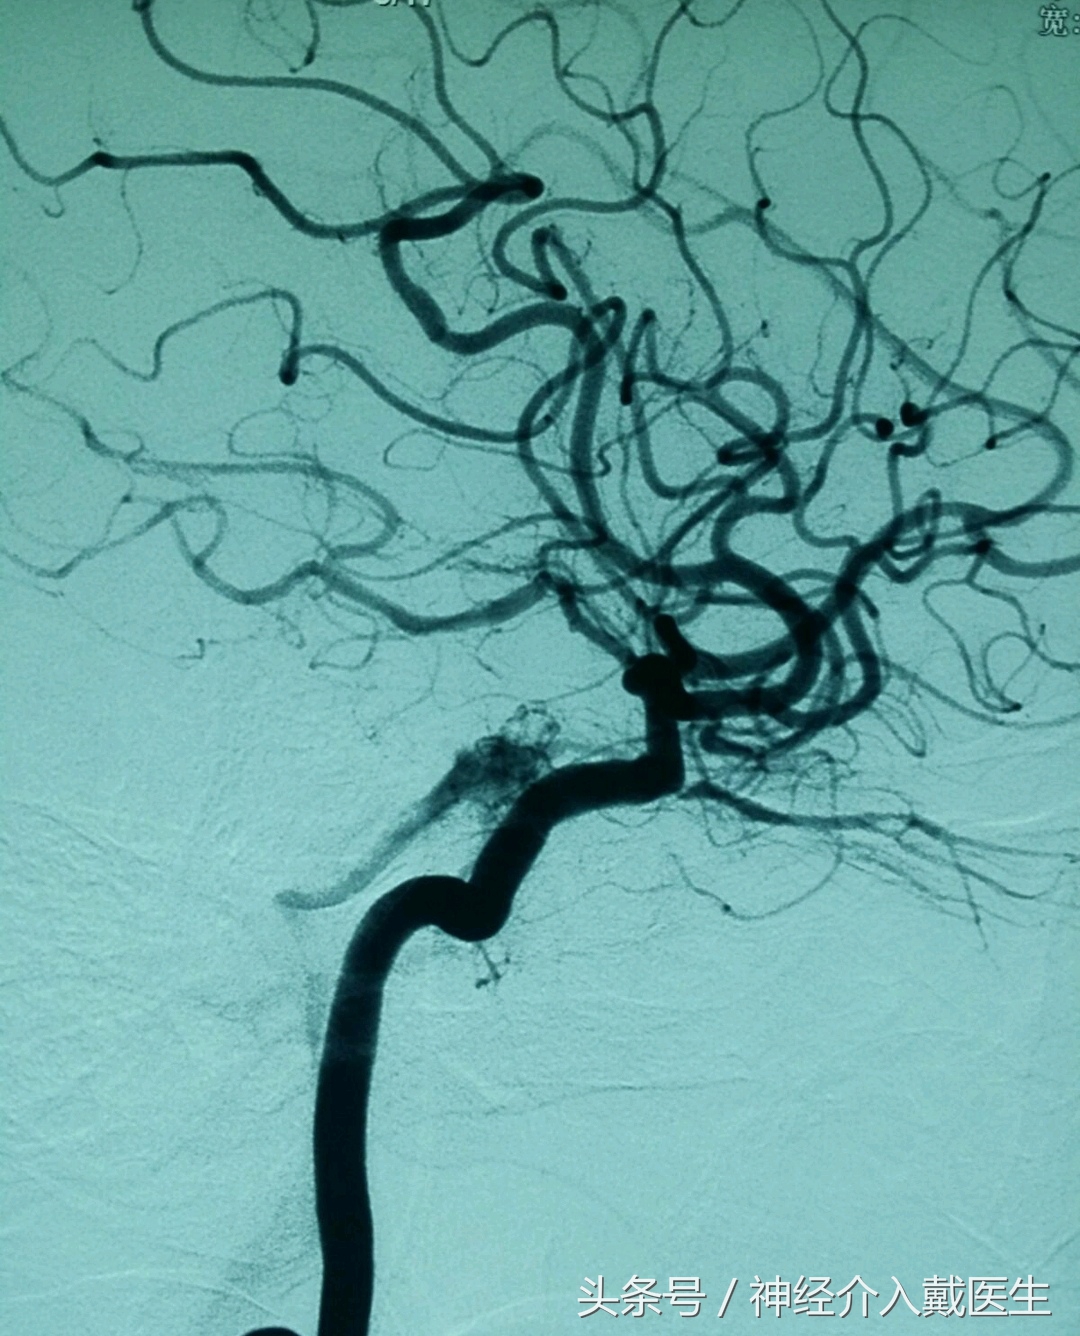

经脑血管介入造影术。果然,右侧颈内动脉海绵窦瘘这个真凶被清楚地展现出来,主要是由于车祸伤导致的颅骨骨折,刺破颈内动脉,导致血流冲向海绵窦内所致。在海绵窦有动静脉,有许多脑神经。